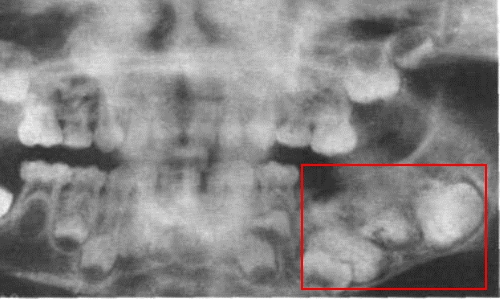

Сначала врач собирает анамнез и проводит пальпацию пораженной области. Затем пациента направляют на рентгенографию. Рентгенологические данные могут указывать на остеокластобластому, но для более точного подтверждения диагноза и выявления возможных метастазов часто назначаются дополнительные исследования, такие как:

Остеокластобластомы возникают в зонах роста как мелких, так и длинных трубчатых костей. Чаще всего опухоли развиваются из тканей бедренной и берцовой костей, реже — в области плечевой кости. Исключительно редко они наблюдаются в верхней и нижней челюстях, костях рук и ног, ребрах и позвоночнике.

Развитие остеокластобластомы в области верхней или нижней челюсти может быть спровоцировано травмами костной структуры или инфекцией, занесенной во время удаления зуба. У женщин с предрасположенностью к этому дефекту вероятность роста опухоли возрастает во время беременности.